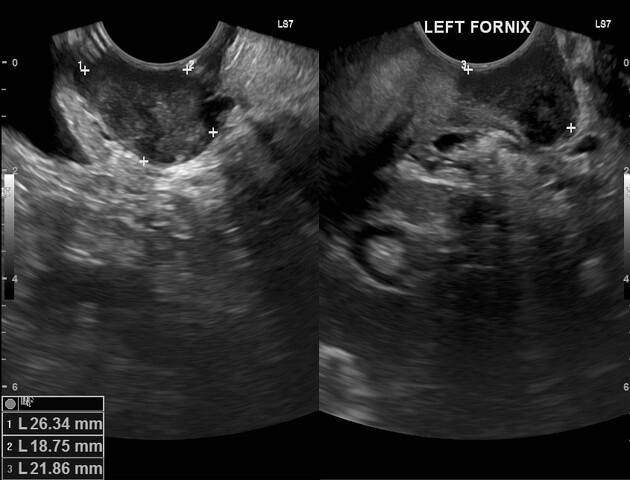

U xơ âm đạo (Vaginal leiomyoma)